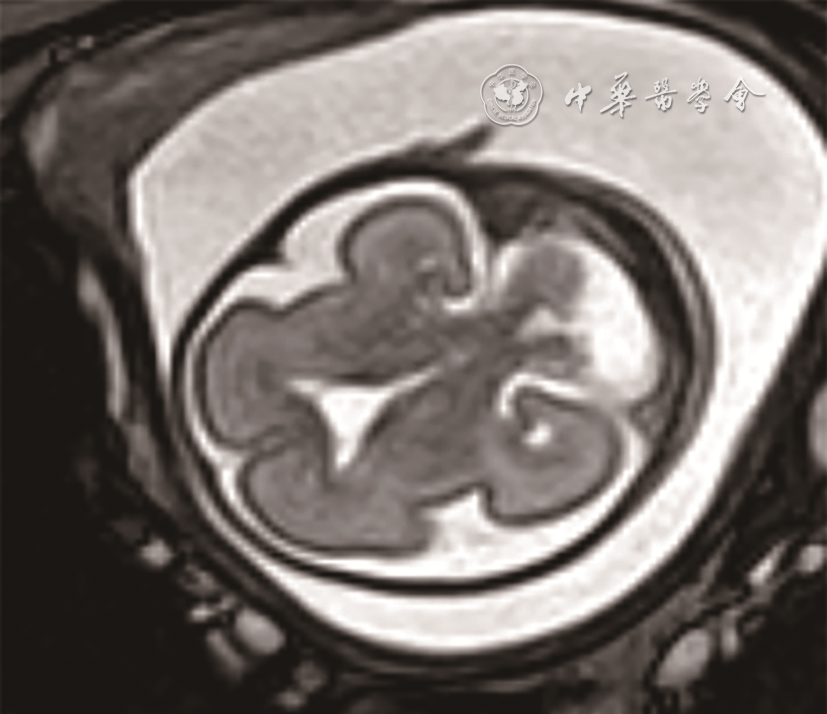

3. 磁共振辅助诊断4例,其中3例胎儿左侧小脑发育不全(图67),1例右侧小脑发育不全。

图6 孕25周胎儿(例5)产前颅脑轴位MRI T2WI 显示左侧小脑半球明显变小

图7 孕23周胎儿(例4)产前颅脑轴位MRI T2WI图像(图a);孕22周胎儿(例6)产前颅脑冠状位MRI T2WI图像(图b)均显示一侧小脑半球明显变小